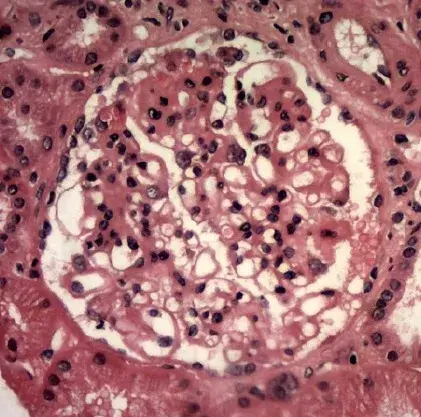

A biópsia renal revelou GN crescêntica necrotizante difusa sem hipercelularidade endocapilar. Alguns raros glomérulos continham células gigantes multinucleadas.

A avaliação da microscopia de luz pode ajudar na diferenciação de casos de **GN por anti-MBG** de casos **GN-ANCA**, já que na GN anti-MBG não observamos hipercelularidade endocapilar e pode ser identificado a presença de células gigantes multinucleadas, estas células gigantes multinucleadas resultam a natureza explosiva e a rápida destruição dos glomérulos observadas em anti-MBG